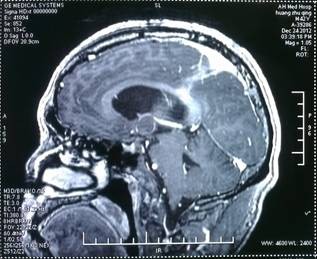

三脑室占位 (术前) (术后)